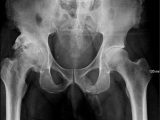

また、人工股関節置換術を受ける予定だったある男性は、骨があまりにも硬すぎてドリルが骨を通らず、あらゆる病院から手術を拒否されるという憂き目に。さらにさらに、クレイトン大学骨粗鬆症研究センターのマーク・ジョンソン氏らは、だれも骨折を経験したことのない米ネブラスカ州の一族を発見しているという。

実はこれらの人物は米東海岸の同じ血筋にあることが分かっており、米イエール大学が彼らのDNAを分析したところ、骨粗鬆症に関係する遺伝子に変異が見られたという。11番染色体にLRP5と呼ばれる遺伝子変異があることで、外部からの刺激に対して骨が繰り返し強化される状態にあるとのことだ。同大学骨研究センター長カール・インソグナ氏も、「彼らは地球上最強の骨を持っています」と絶賛するほどの硬さだ。